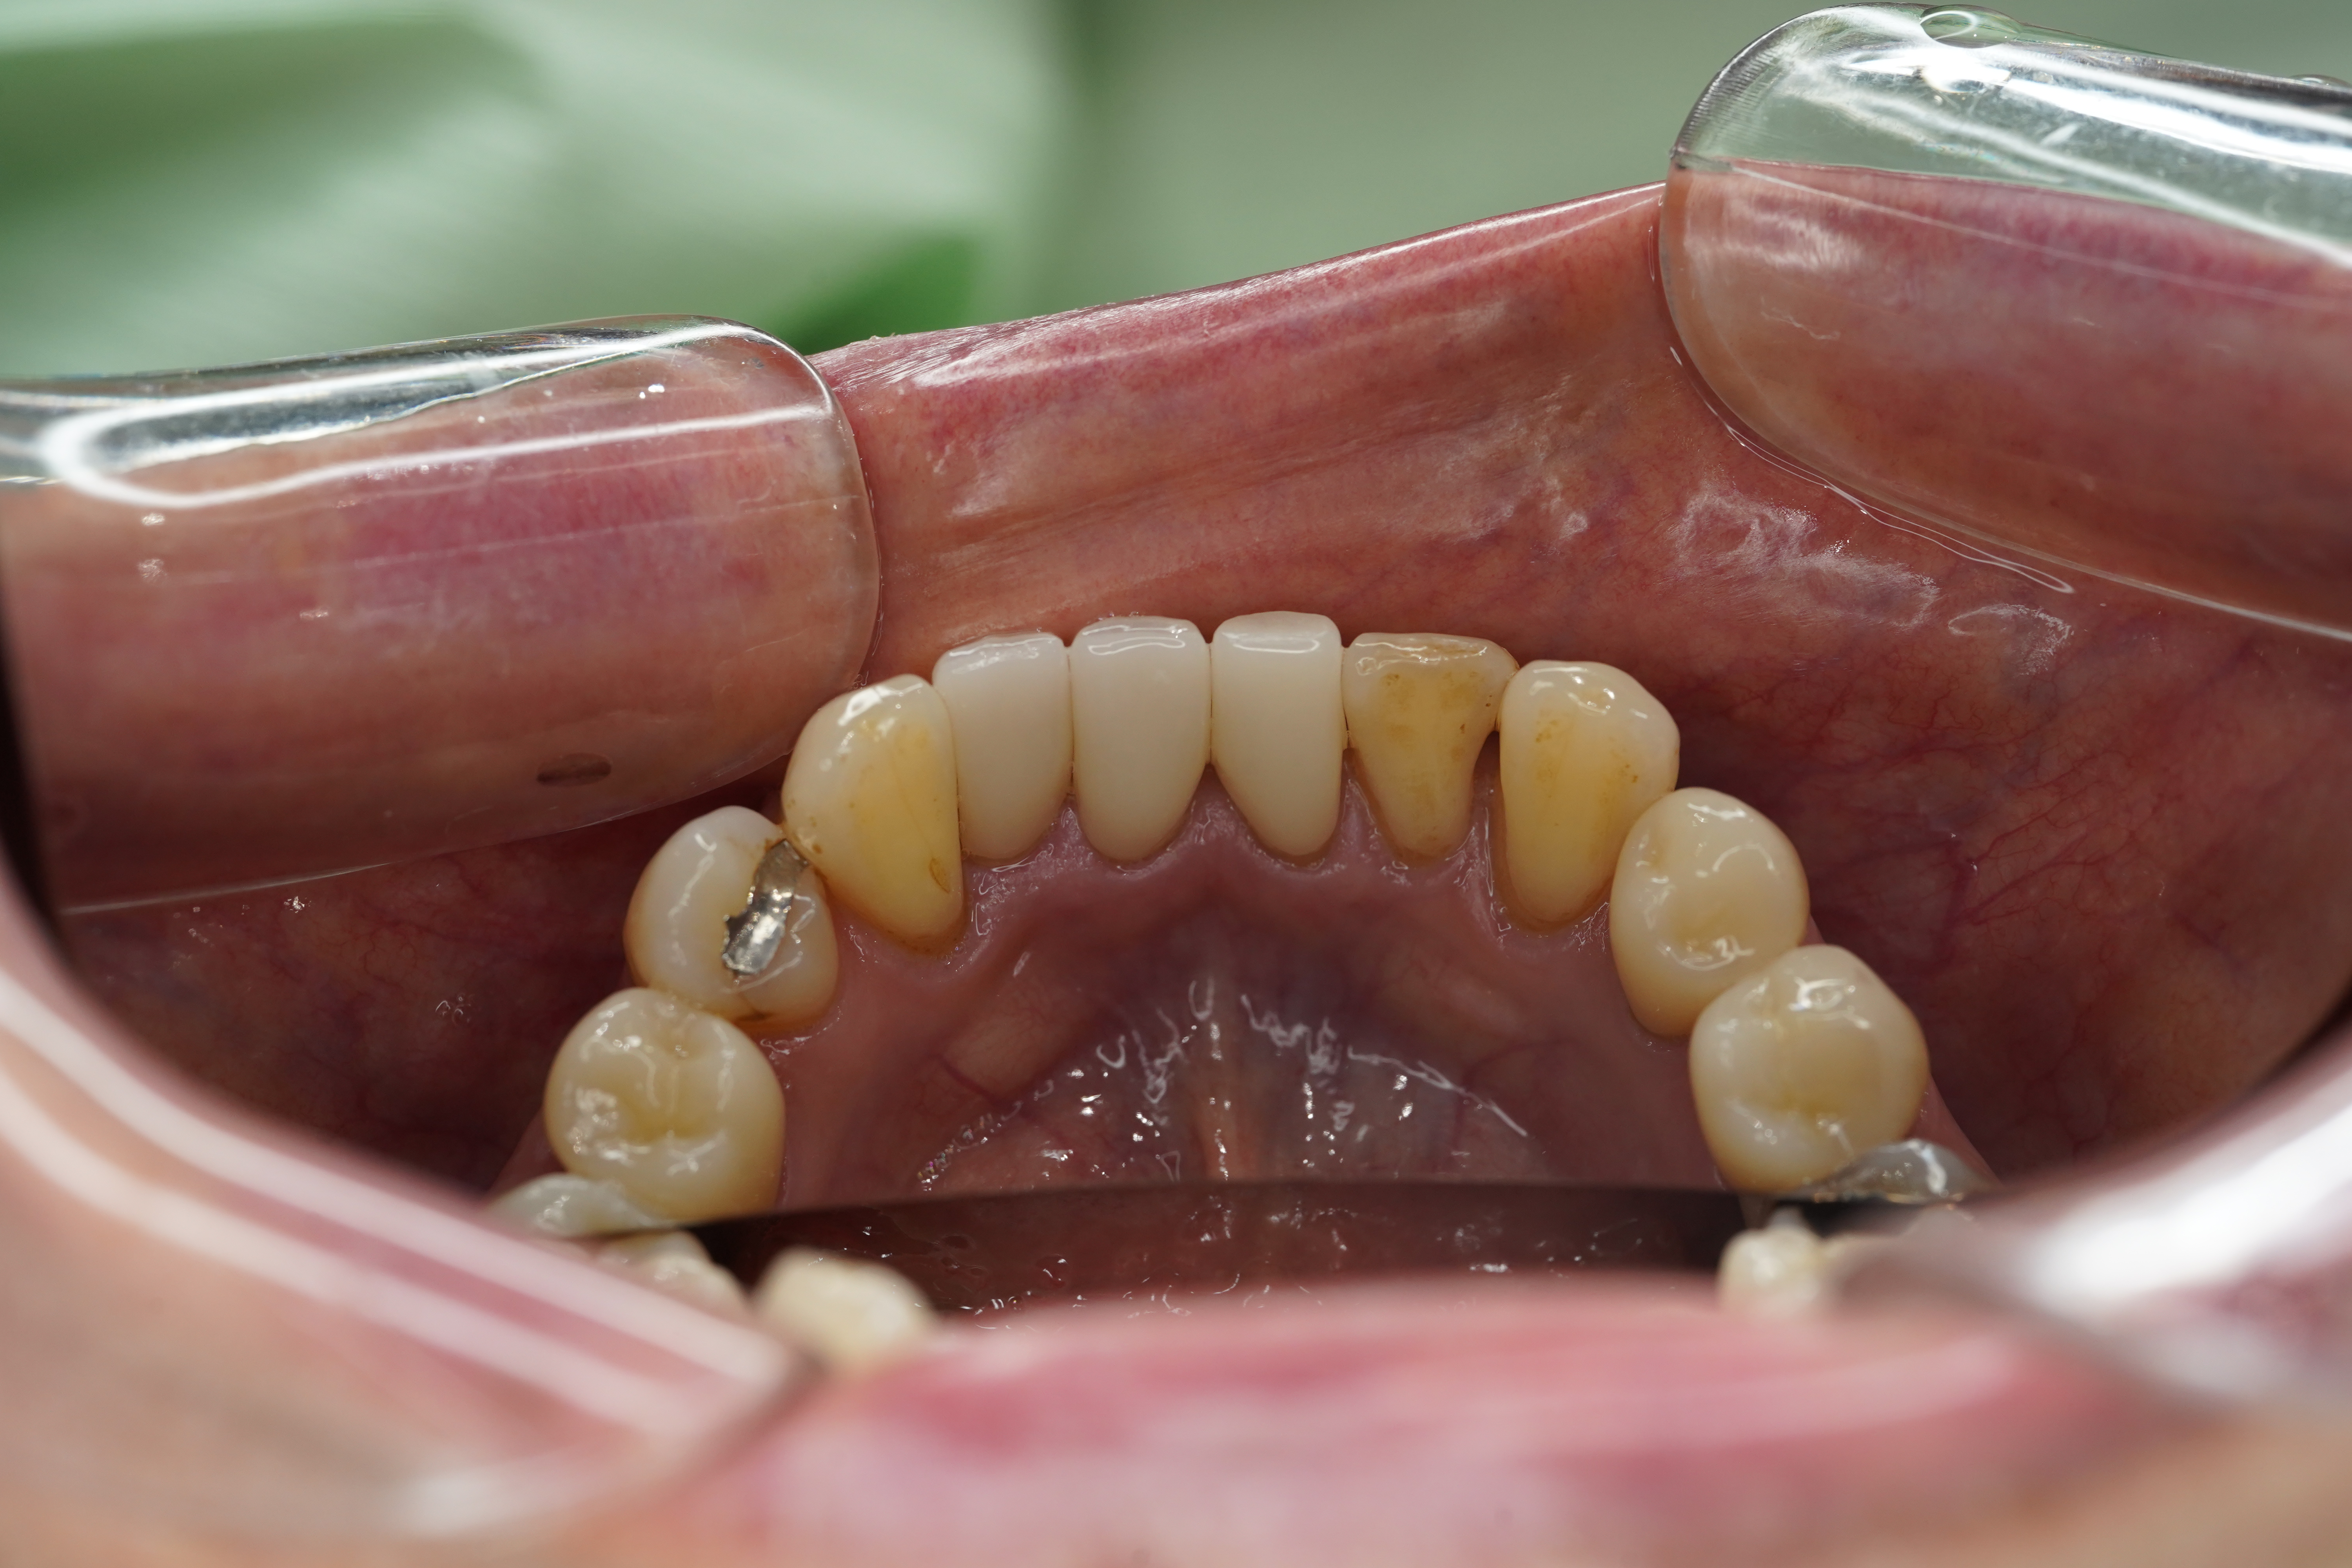

こちらが処置前Photoになります

右下中切歯にメタルとその両隣の歯に虫歯が、また並びが重なっていてそこも気になる!とのことで治療することとなりました

神経は生きていたのでMTA自体は可能でしたが、下顎前歯はもともとサイズが小さいためMTAで神経保護を行うと被せ物の脱離の可能性が大きくなるので、精密に根管治療を行いファイバーコアを立てジルコニアセラミックで被せることとなりました